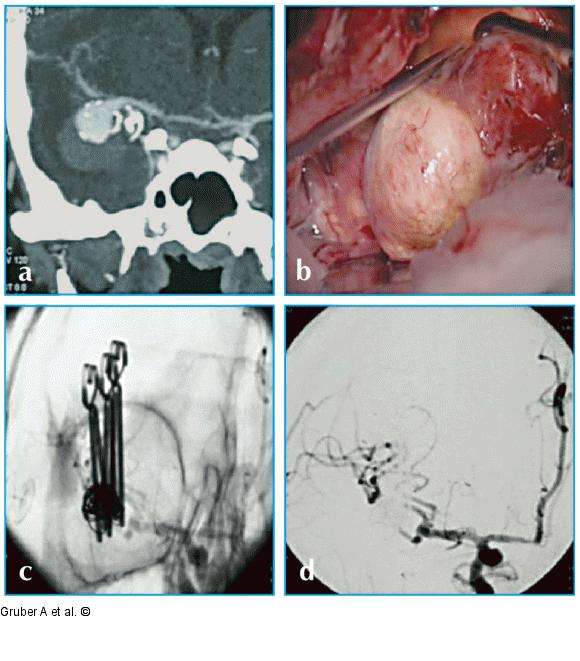

Abbildung 3a-d: Mikrochirurgische Klippung Mikrochirurgische Klippung. (a) Präoperative CT-Angiographie, (b) intraoperative Exploration, (c) mikrochirurgische Klippung sowie (d) Dokumentation des Verschlusses durch intraoperative DSA bei teilthrombosiertem, vorembolisiertem Mediabifurkationsaneurysma rechts. |

Mikrochirurgische Klippung. (a) Präoperative CT-Angiographie, (b) intraoperative Exploration, (c) mikrochirurgische Klippung sowie (d) Dokumentation des Verschlusses durch intraoperative DSA bei teilthrombosiertem, vorembolisiertem Mediabifurkationsaneurysma rechts. |